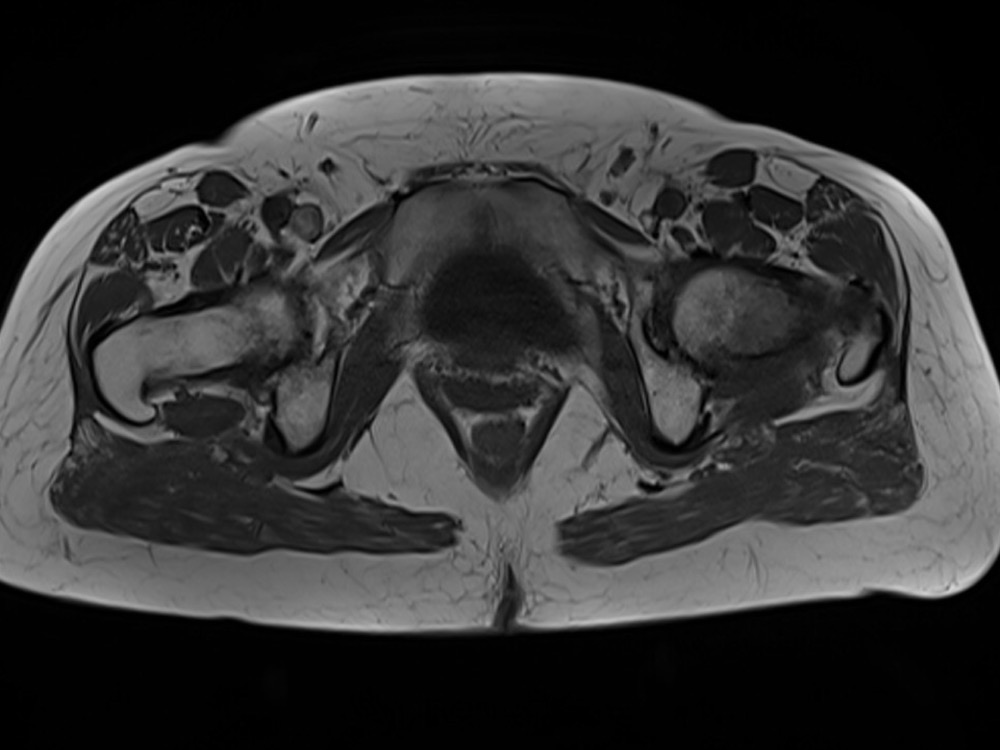

Douleurs de hanche

Linda Ouerd 06/11/2019